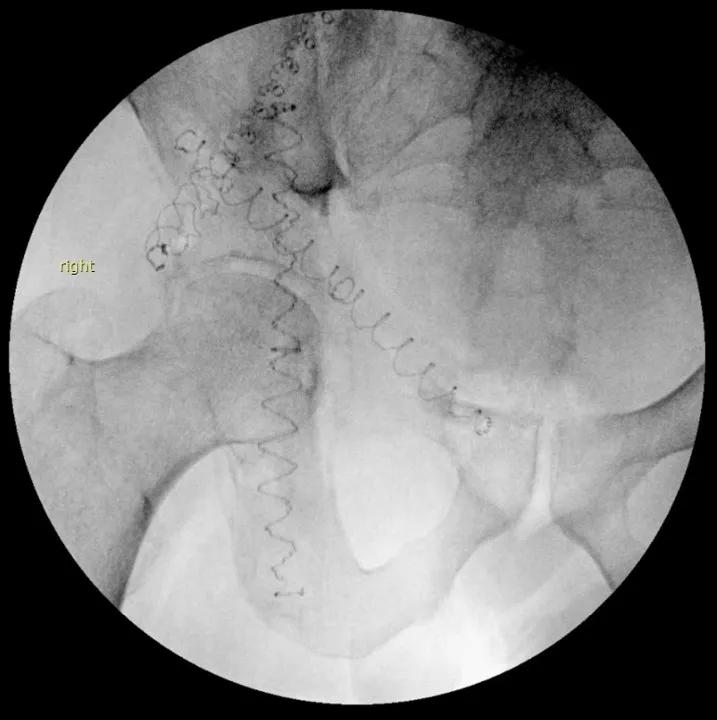

Kyphoplasty of acetabulum

Intraoperative anterior-posterior fluoroscopy shows three photodynamic balloons supporting the right acetabulum. This procedure also can be done with cannulated screws. Balloons were chosen in this case to help fill some of the metastatic defect in the acetabulum.